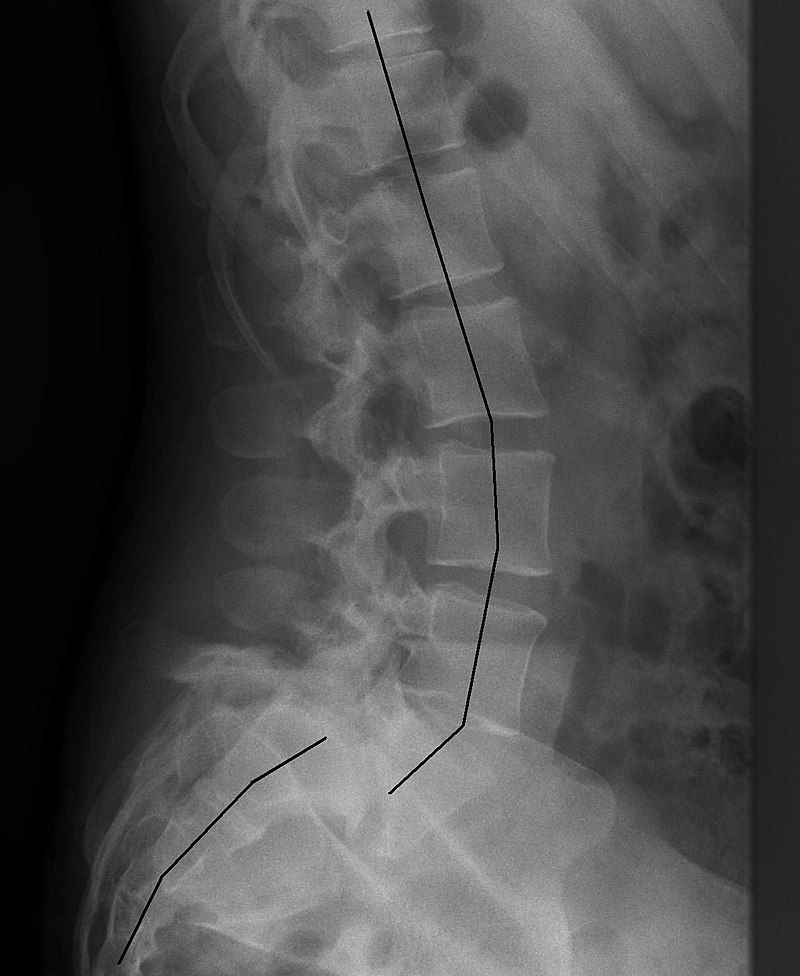

척추전방전위증의 엑스레이(x-ray) 촬영 이미지